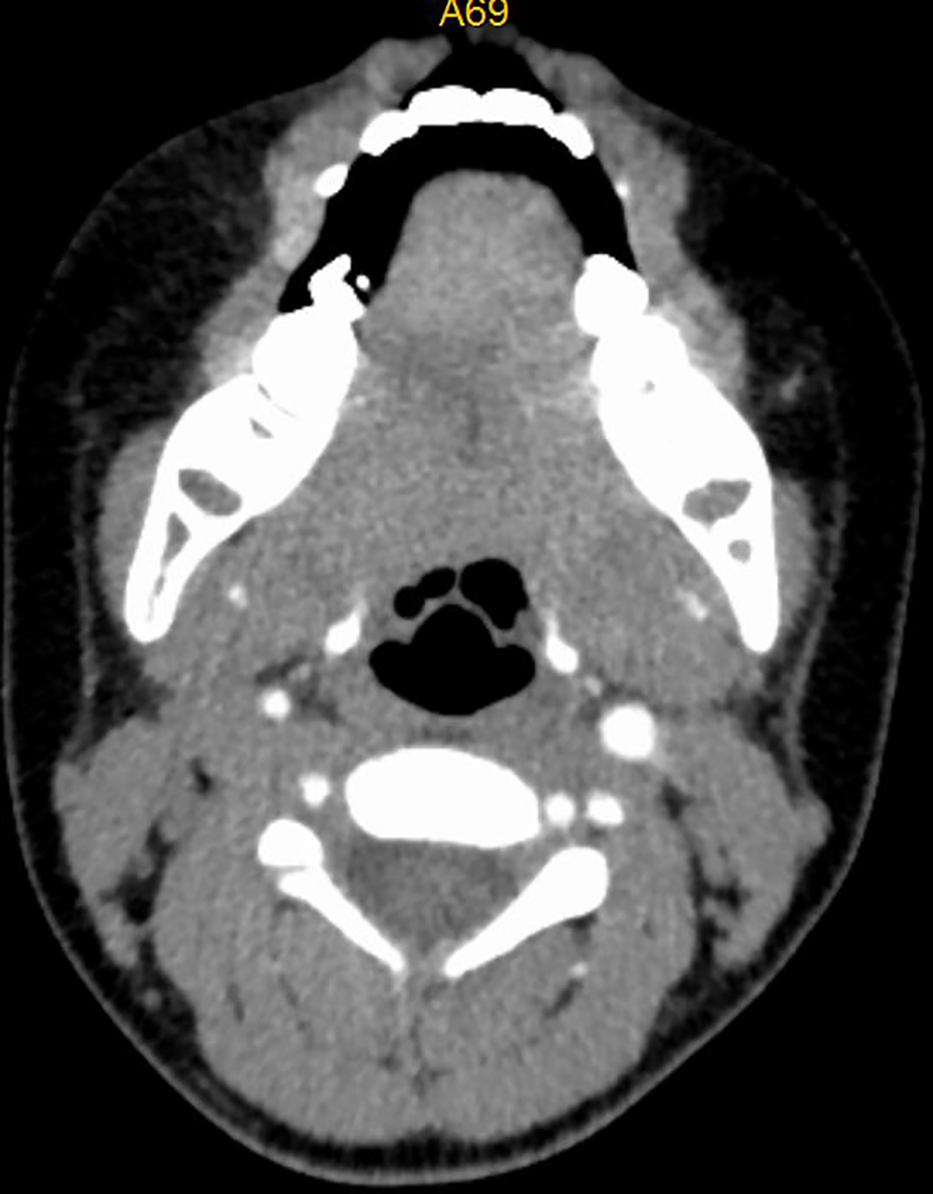

Figure 1

CT image of No. 8 patient before embolization treatment, with marked enhancement of hemangioma and airway stenosis.